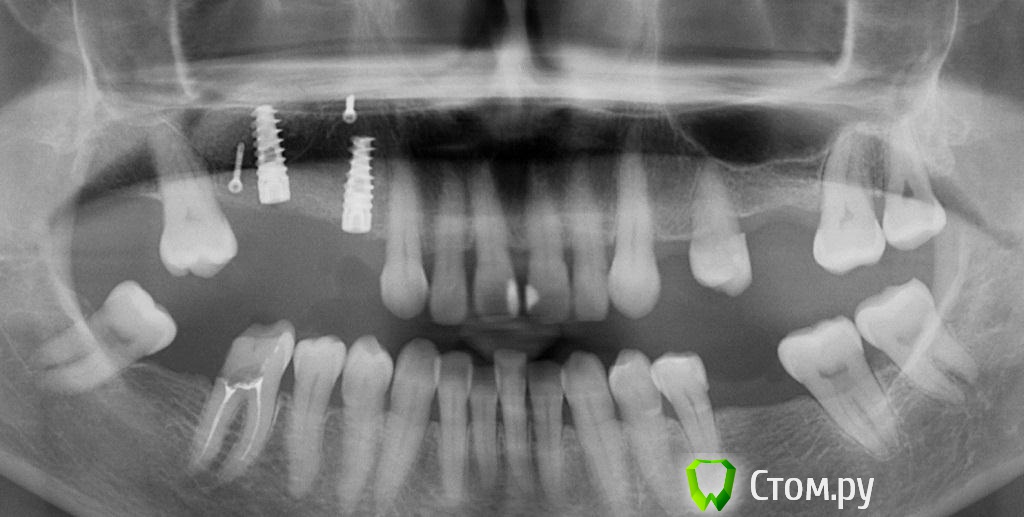

zzkz Опубликовано 18 апреля, 2014 Поделиться Опубликовано 18 апреля, 2014 Спасибо коллегам за вдохновение! Хотя есть не радующие моменты, шел на риск. Фото третьего ассистента немного размыто. Пока не получается отладить(в процессе) Синус+ Небольшое расщепление+ био осс под Ламину.Швы толстые викрил 4-0 - другого не оказалось под рукой, был Пролен 6-0(сомнения что прорежут слизистую) Из вопросов которые возникли 1. винтов не оказалось маленьких(выяснилось во время операции), пришлось фиксировать на винты длиной 10мм в графт в пазухе.что то из за этого может произойти как думаете? 2. импланты с нулевым торком(не надо было делать пропилы), рукой установил, боялся даже заглушку сильно крутить? не чревато ли? 3. Импланты вроде ставил параллельно, а на снимке корявенько, панорамник что ли врет? 1 Ссылка на комментарий

zzkz Опубликовано 19 апреля, 2014 Автор Поделиться Опубликовано 19 апреля, 2014 (изменено) нулевой торк - это сколько? крутится пальцами легко легко? Если хоть небольшое усилие есть - все ок. Над фотопротоколом надо поработать )))да про фото вы говорили. В профессе работы об этом забываю, а асси боится попросить дать ей пару секунд фото сделать))совсем совсем нулевой, пальцами без особых усилий((кстати вам отдельное спасибо за курс в течении 2-3 месяцев нужно исключить малейшее накусывание чего либо в этой области.. иначе, в связи с нулевым торком, можете получить "плавающие" в пазухе имплантатыспасибо за совет! Изменено 19 апреля, 2014 пользователем zzkz Ссылка на комментарий